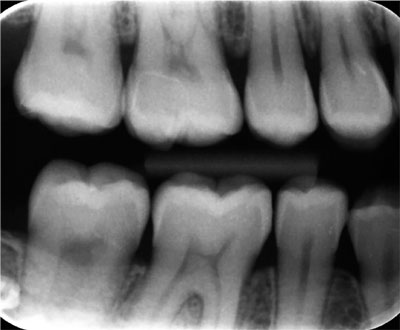

As a consequence of increased dental awareness in society, coupled with improvements in dietary and oral hygiene practices, many more patients, particularly younger patients, are now presenting with fewer and smaller lesions of caries than in the past (Figs 1-1 and 1-2). Such patients expect minimally interventive procedures, preferably using techniques that are described as “aesthetic” or “tooth coloured” (Fig 1-3). This, in association with commercial developments in composite resin materials and associated bonding technologies and lingering concerns over the safety of dental amalgam, has driven an increase in the placement of posterior composite restorations in general dental practice. For example, a survey of United Kingdom general dental practitioners in 2001 revealed, far from limiting the placement of composite to small cavities in premolar teeth, that almost one-half of general dental practitioners placed composite resin restorations in load-bearing cavities in molar teeth (Figs 1-4 to 1-6).

Fig 1-2 Bitewing radiograph from a healthy 35-year-old female demonstrating an absence of caries or restorations.